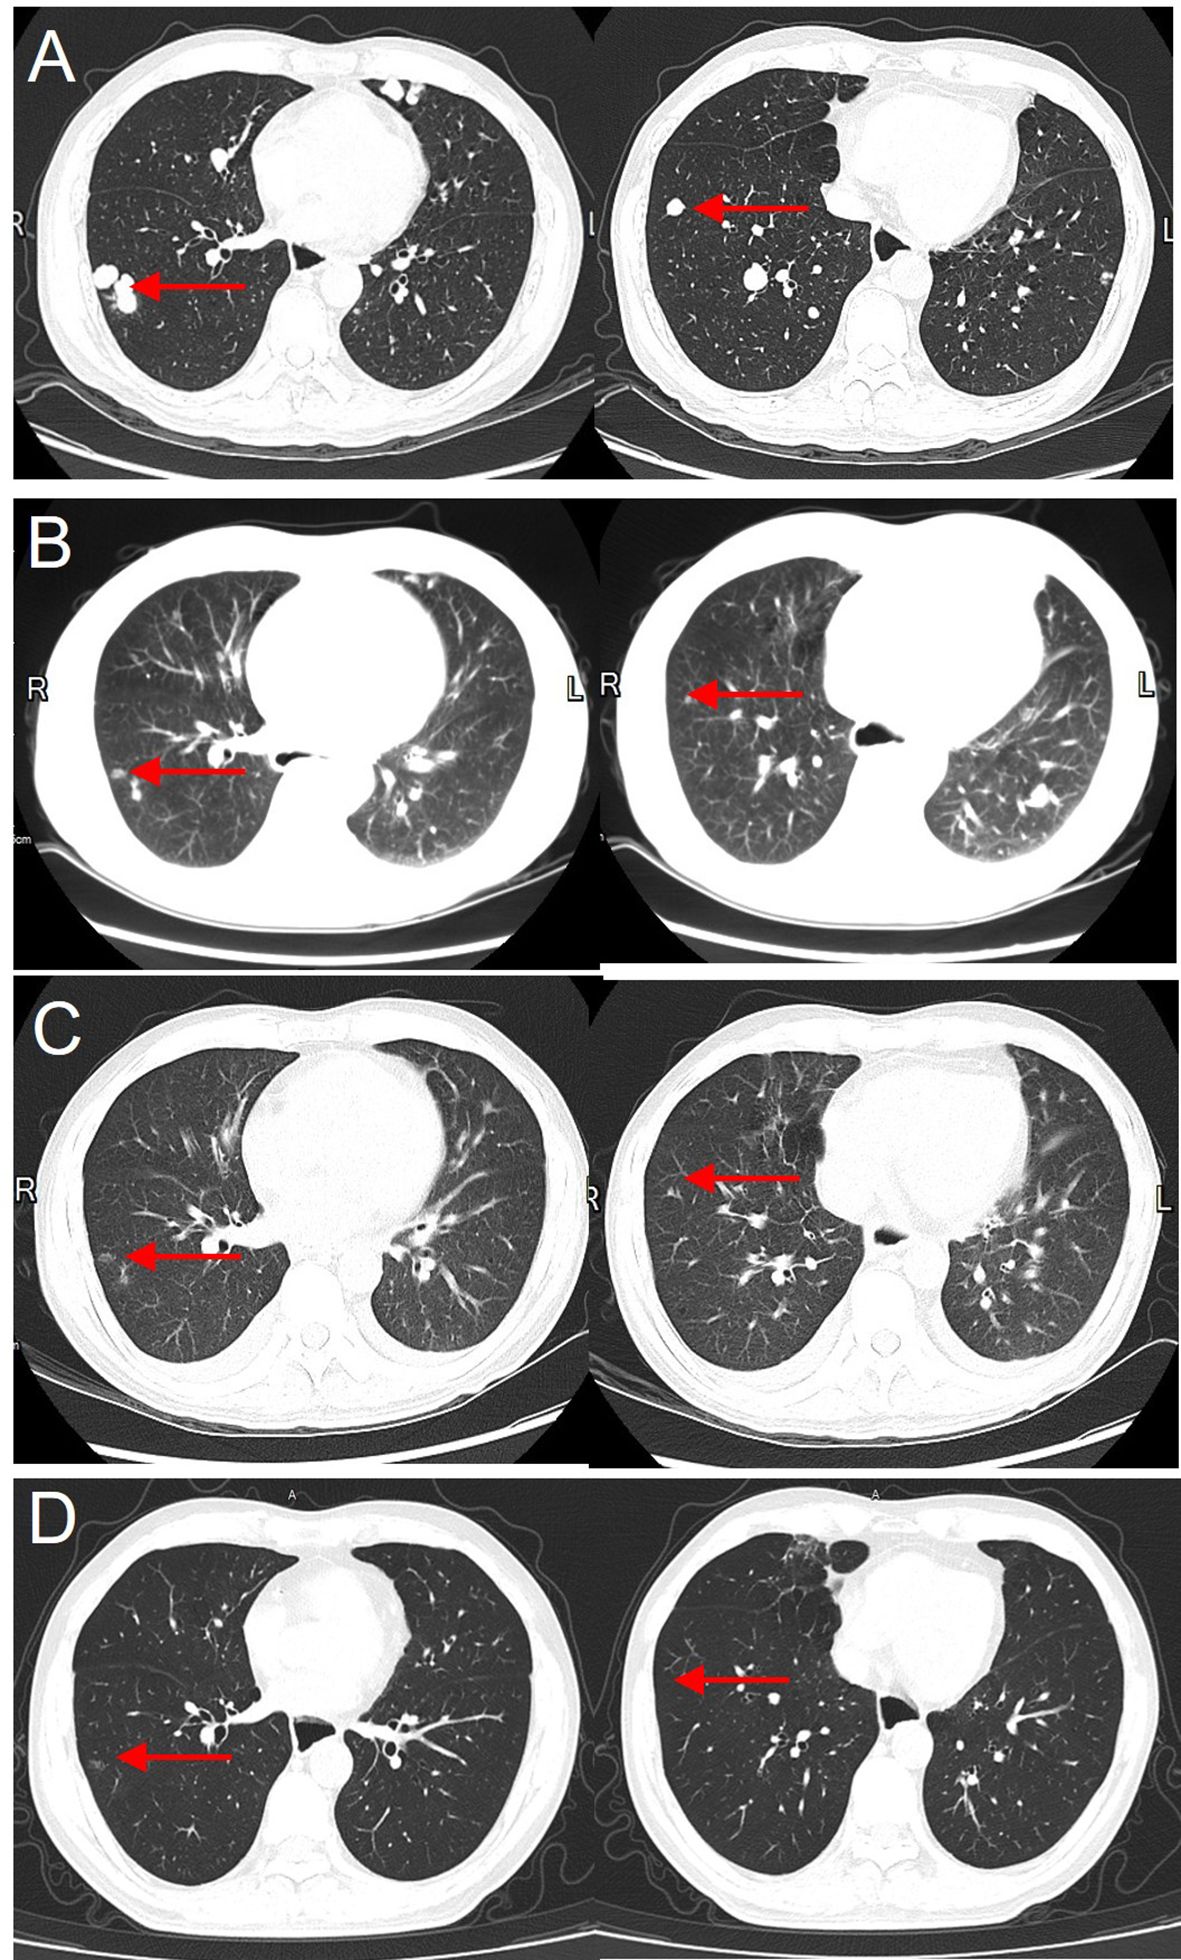

Figure 3

Gradual disappearance of lung metastases following PD-1 inhibitor therapy, with no recurrence after 7 years. (A) Pre-treatment CT showing the largest lung metastasis with a diameter of 1.5 cm before starting PD-1 inhibitor therapy. (B) Two months after PD-1 inhibitor therapy, the lung metastasis has significantly reduced in size. (C) Four months after treatment, the lung metastasis is nearly completely resolved. (D) Seven years after PD-1 inhibitor therapy, follow-up chest CT shows no recurrence of lung metastases.

At postoperative week 2, the patient underwent prophylactic transarterial chemoembolization (TACE). Systemic therapy with sorafenib was initiated but demonstrated poor tumor control, and intrahepatic recurrence with pulmonary metastases was detected at six months postoperatively (Figure 3). Thereafter, sorafenib was discontinued, and the patient underwent additional TACE (Supplementary Material 2) and FOLFOX4 chemotherapy. At postoperative month 10, thymosin α1 was introduced as an adjuvant therapy; however, The disease exhibited continuous progression despite treatment.

After two cycles, follow-up imaging revealed evident tumor regression accompanied by a substantial decline in AFP levels (Figure 4), indicating a strong anti-tumor response. Following four cycles of PD-1 inhibitor therapy, the patient achieved complete remission (CR) and subsequently discontinued treatment entirely. Following the third dose, the patient developed hypothyroidism, gastrointestinal toxicity (severe diarrhea), poor appetite, and psychiatric symptoms including hallucinations. These symptoms markedly improved following glucocorticoid therapy.

Subsequent follow-up imaging confirmed the absence of tumor recurrence or metastasis, AFP levels returned to normal, and PET-CT scans confirmed a complete metabolic response (CMR).